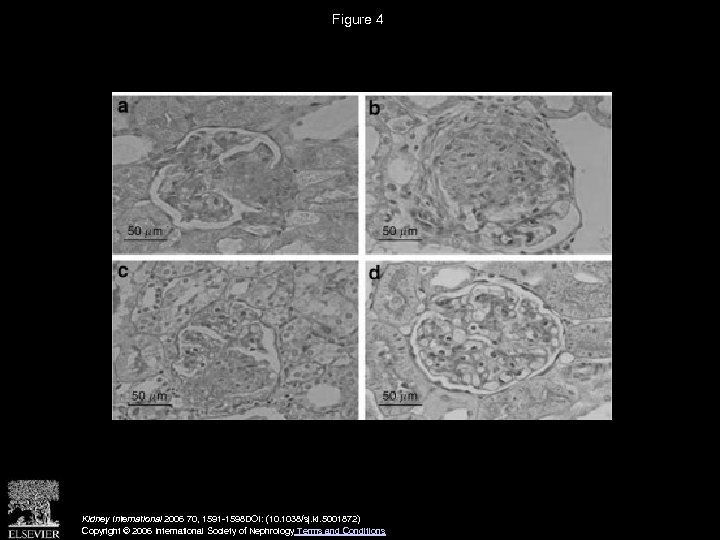

Figure 4 Kidney International 2006 70, 1591 -1598 DOI: (10. 1038/sj. ki. 5001872) Copyright © 2006 International Society of Nephrology Terms and Conditions